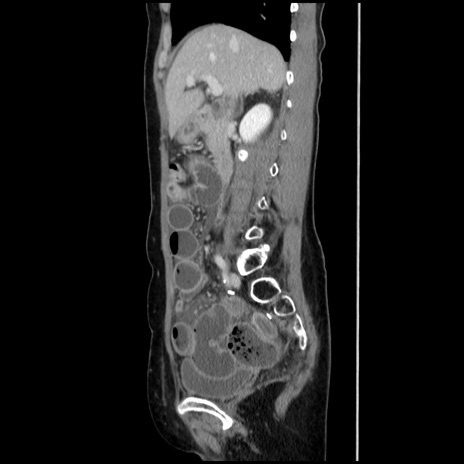

症例32(矢状断像)

【症例】40歳代 女性

【主訴】上腹部痛、嘔気・嘔吐

【現病歴】約9時間前頃から急に上腹部痛、嘔気、嘔吐が出現。改善しないため救急要請。

【既往歴】子宮頚癌(広汎子宮全摘術、放射線療法)、腸閉塞

【身体所見】腹部:平坦、軟、腸雑音亢進、上腹部を中心に腹部全体に圧痛あり。

【データ】WBC 8400、CRP 0.03

横断像